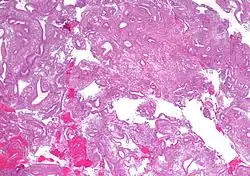

| Micrograph showing simple endometrial hyperplasia, where the gland-to-stroma ratio is preserved but the glands have an irregular shape and/or are dilated. Endometrial biopsy. H&E stain. | |

Like other hyperplastic disorders, endometrial hyperplasia initially represents a physiological response of endometrial tissue to the growth-promoting actions of estrogen. However, the gland-forming cells of a hyperplastic endometrium may also undergo changes over time which predispose them to cancerous transformation. Several histopathology subtypes of endometrial hyperplasia are recognisable to the pathologist, with different therapeutic and prognostic implications.[4]

- Endometrial hyperplasia (simple or complex) - Irregularity and cystic expansion of glands (simple) or crowding and budding of glands (complex) without worrisome changes in the appearance of individual gland cells. In one study, 1.6% of patients diagnosed with these abnormalities eventually developed endometrial cancer.[7]